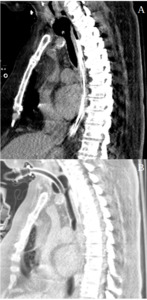

Postoperative CT imaging illustrated the repaired tracheal and esophageal sites, demonstrating tissue edema and inflammation at the repair locations. The repositioned tracheostomy tube minimized pressure on the reconstructed tracheal segment, as shown in Figure 2A and 2B.